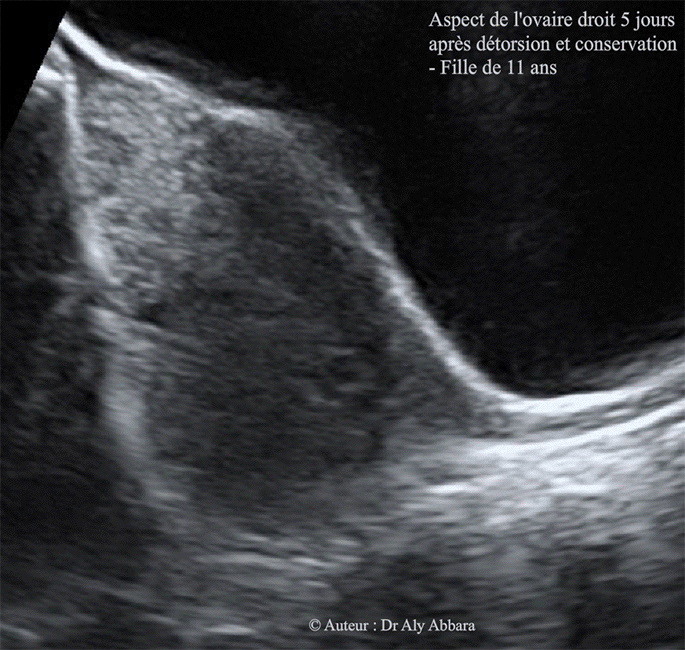

J5 :

Images échographiques montrant le même ovaire droit, cinq jour après la détorsion chirurgicale et la conservation des annexes droites : on remarque une diminution de son volume (34,7 x 29 x 34 mm, soit environ 18 cm3 contre 73 cm3 en pré-opératoire).

L'écho-Doppler n'a pas permis de confirmer de la présence des signaux Doppler vasculaires).